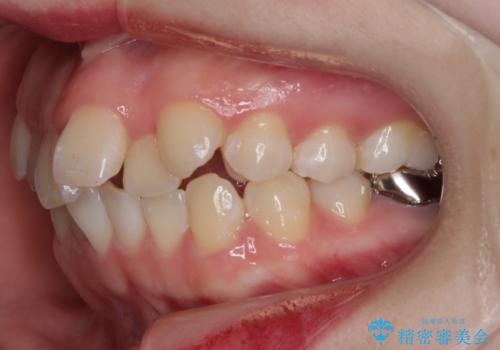

- 前歯のガタつきと口元の改善を主訴に来院されました。

なるべく目立たない装置が良いというご要望と、口元を引っ込めたいというご要望を両方達成するために今回はハーフリンガル装置を選択し治療計画の立案を行いました。

結果的に表の装置よりは期間が掛かりましたが、口元もしっかり下がり韓国美人な横顔になったと患者様にも喜んでいただけました。